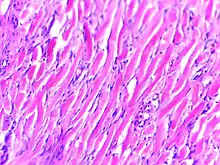

Micrograph of keloid. Thick, hyalinised collagen fibres are characteristic of this aberrant healing process. H&E stain.

Histologically, keloids are fibrotic tumors characterized by a collection of atypical fibroblasts with excessive deposition of extracellular matrix components, especially collagen, fibronectin, elastin, and proteoglycans. Generally, they contain relatively acellular centers and thick, abundant collagen bundles that form nodules in the deep dermal portion of the lesion. Keloids present a therapeutic challenge that must be addressed, as these lesions can cause significant pain, pruritus (itching), and physical disfigurement. They may not improve in appearance over time and can limit mobility if located over a joint.